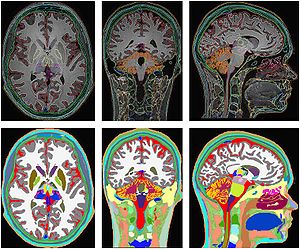

The regions-of-interest (ROIs) were manually drawn by an experienced radiologist by using the b 1000 images, averaged for all measured directions, the FA maps and the proton-density weighted images. For that purpose, the maps of ADC, FA, R2 and R2* as well as the proton-density weighted images were first co-registered. The ROIs were segmented by syncing the b 1000 images, averaged for all measured directions, the FA maps and the proton-density weighted images in ImageJ. The ROIs were stored in the ROI manager and transferred to the co-registered maps. The segmented brain regions were highlighted in different colors: CN—black; PU—red; GP—green; TH—white; SN—blue; CC—cyan. The diffusion-weighted images, the R2 and R2*-weighted maps were transferred to the 3D Slicer software in order to co-register the R2 and the R2* maps as well as the MD and the FA maps |